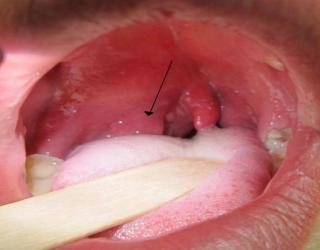

स्वास्थ्य : Coronavirus: गले की खराश, खांसी, जुकाम, बुखार जैसे कोरोना और फ्लू के लक्षणों को खत्म करने के लिए चबाएं ये 6 चीजें